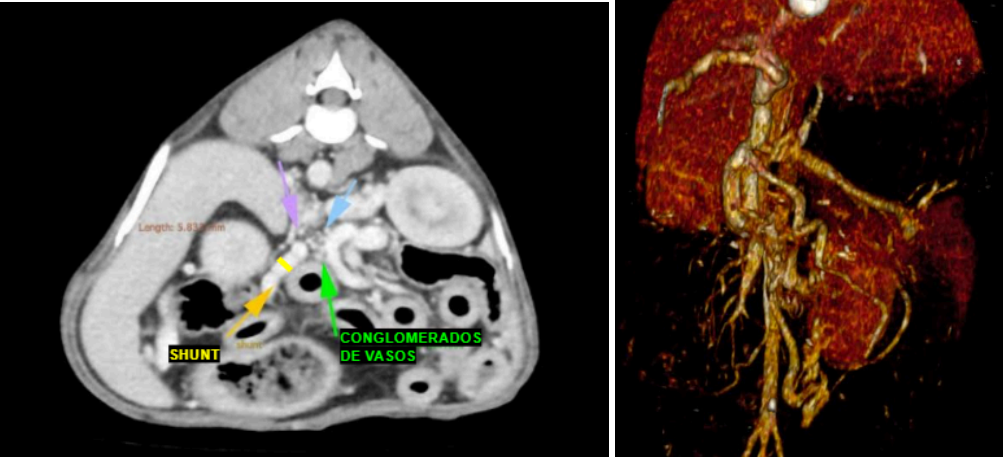

A Tomografia Computadorizada Angiográfica (Angio-TC) evidenciou desvio portossistêmico extra-hepático congênito do tipo esplenorrenal esquerdo, caracterizado por vaso tortuoso originado da veia esplênica e conectado à veia renal esquerda, além da presença de varizes frênicas, indicativas de circulação colateral adquirida associada à hipertensão portal crônica. Este padrão combinado é compatível com casos descritos na literatura em que o shunt congênito evolui com o desenvolvimento de colaterais compensatórias (RICCIARDI, 2016)

Figura 4 – Tomografia Computadorizada Angiográfica de Abdômen Total Contrastado

O caso relatado descreve um cão adulto, SRD, diagnosticado com desvio portossistêmico extra-hepático do tipo esplenorrenal, associado à formação de colaterais adquiridas, entre elas varizes frênicas, configurando um quadro compatível com shunt congênito que evoluiu para hipertensão portal e desenvolvimento de circulação colateral secundária. Esse padrão hemodinâmico já foi relatado em estudos que demonstram a possibilidade de coexistência entre conexões congênitas e vias adquiridas em cães com redução crônica do fluxo portal. Estudos mostram que alguns cães com shunts congênitos desenvolvem varizes colaterais adicionais quando o fígado permanece hipoperfundido por anos (RICCIARDI, 2016; BERTOLINI, 2010; BERTOLINI, 2019).

O baço, no ultrassom, mostrou alterações de ecogenicidade e padrão parenquimatoso alterado. Mesmo que a tomografia tenha descrito dimensões dentro da normalidade, as alterações funcionais vistas no US e a presença de varizes frênicas na tomografia reforçam a ideia de congestão crônica do fluxo esplênico. Na fisiopatologia do shunt esplenorrenal, o sangue que deveria ir para a veia porta passa diretamente pelo vaso anômalo, porém o fluxo não é tão eficiente quanto seria pela porta, devido ao grande volume sanguíneo drenado dos órgãos abdominais e ao calibre do vaso não ser suficiente para suportar tamanho volume sanguíneo. Isso causa lentificação na drenagem e mudanças texturais no baço, como já descrito por Bertolini (2019). O conjunto entre achado ultrassonográfico e a região de microvasos neovasculares observada na TC sugere que o baço realmente estava participando de um processo de angiogênese devido a congestão sanguínea causada pela lentificação na drenagem, com um remodelamento vascular para suprir essa pressão sanguínea.

A tomografia computadorizada (TC) com contraste foi essencial para a definição diagnóstica, permitindo a visualização detalhada do shunt esplenorrenal e das varizes frênicas associadas. Estudos demonstram que a TC apresenta sensibilidade e especificidade superiores quando comparada à ultrassonografia, sendo considerada o padrão ouro para detecção, caracterização anatômica e planejamento cirúrgico dos DPSEH (KIM et al., 2013; ZWINGENBERGER et al., 2005; POSASTIUC et al., 2022). A presença de vasos colaterais adquiridas no exame tomográfico reforça a hipótese de hipertensão portal crônica, concordando com relatos que descrevem padrões semelhantes em cães com alterações vasculares prolongadas (BERTOLINI, 2010; 2019).